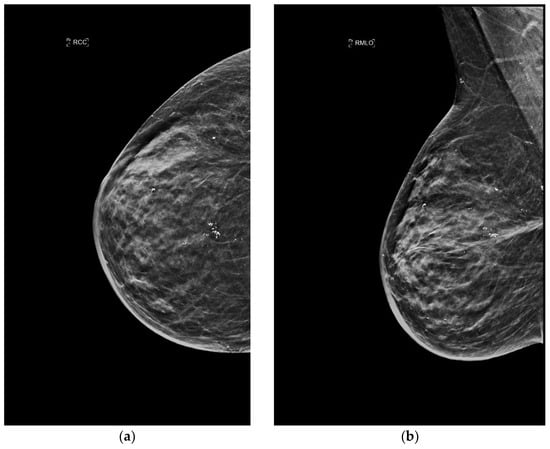

4.1. Mammography